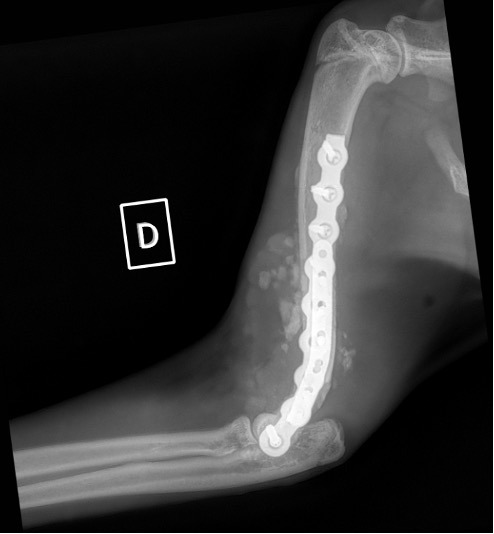

Notre préférence va vers le placement de deux plaques humérales : une médiale de la plus grande taille possible et l’autre latérale, généralement d’une taille inférieure à la première. Dans l’exemple 1 (chat européen), une plaque de 2 mm est utilisée médialement et une plaque de 1,5 mm latéralement. Dans l’exemple 2 (chien Malinois), une plaque de 3,5 mm est utilisée médialement et une plaque de 2,7 mm latéralement.

Exemple 2 :

Figure 4 : Pré-Op

Figure 5 : Post-Op Immédiat

Figure 6 : Post-Op 1 mois

Figure 7 : Post-Op 2 mois